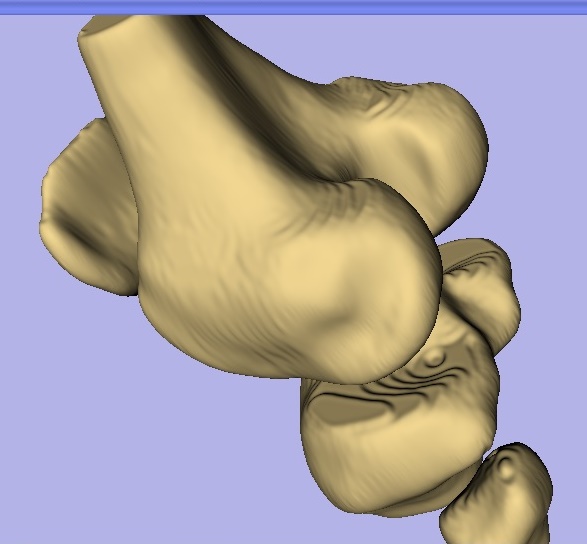

We have our file! But wait… we still need to clean it up a little bit so it doesn’t look so rough around the condyles (see what I did there?). To do that I use a software called meshmixer, which is SURPRISE! also free. Once you install and open Meshmixer, select File and then Import. Select the Model.stl file (or whatever you named it) and open it. It should look like what I have below, which I changed the color to make it easier to see, you can do this by selecting shaders and selecting the profile you like best.

Now that we have it opened, we can finish processing the model. Click the Sculpt button on the left and select Robust Smooth (red circle). You can adjust the strength of the tool, size, depth, and several other parameters from the window shown here in the middle. I would suggest staying with the default until you are comfortable with the program.

As you can see below the red dot is the center of the brush tool and the white semi-transparent sphere is the range of the tool. Start smoothing the areas you feel need to be smoothed (this will depend on your model). Take it slow and don’t over smooth or you’ll end up with something… less than accurate.

Once you have finished smoothing you should have something that looks similar to what is shown below. Now that you are finished you can save the file as a Meshmixer file (this way if you need to go back and rework the model, you will not have to start from scratch). Lastly under the file menu in the top left hand corner, you can select export which will allow you to export your model as an STL file.